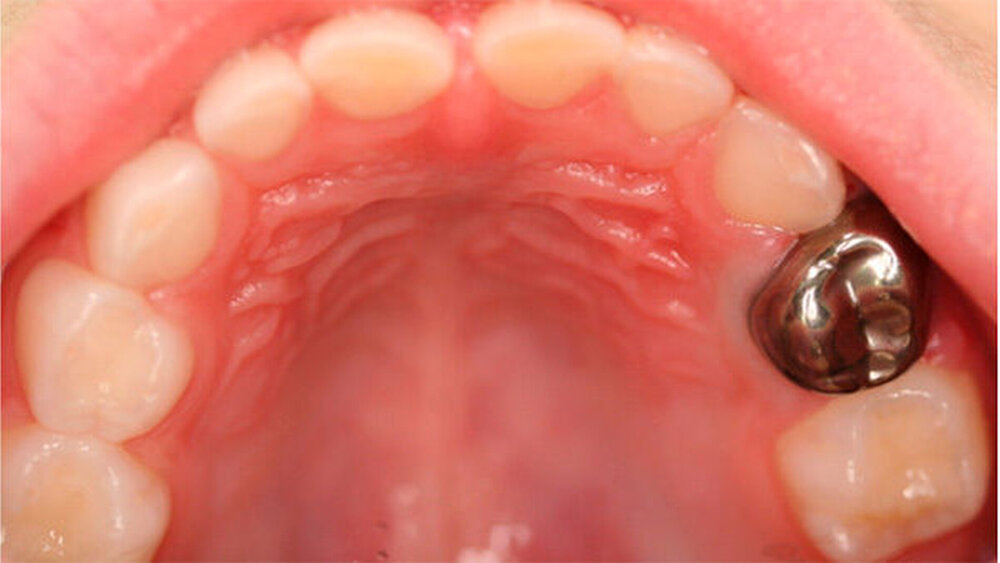

Bei kontinuierlicher Symptomfreiheit des Zahns 64 und Einwilligung wurde angeboten, nach einer weiteren Desensibilierungs- und Prophylaxesitzung den kariösen Zahn „ohne bohren“ mithilfe der Hall-Technik zu therapieren. Die Mutter und das Kind wurden über die Technik umfänglich aufgeklärt. Zur Vorbereitung des Kindes auf die Therapie wurden Lexeme wie „Prinzessinnenzähne“ oder „Königskronen“ benutzt. Im Rahmen der Hall-Therapie wurde keine Lokalanästhesie, Präparation des Zahnes oder Kariesentfernung durchgeführt [Evans & Innes, 2010].

Für den Zahn wurde eine konfektionierte Stahlkrone (Größe 5) ausgewählt. Nach Reinigung des Zahnes wurde die konfektionierte Stahlkrone mit dünnfließendem Glasionomerzement zementiert. Dabei ist es wichtig dass die Krone den Zahn komplett bedeckt und die Ränder epi- bis leicht subgingival liegen (Abb. 2 a, b, c). Eine temporäre Bisserhöhung von circa zwei Millimetern ist häufig und korrigiert sich wie in diesem Fall in den ersten Wochen nach Applikation der Krone wieder vollständig [Van der Zee & van Amerongen, 2010].

Die Kooperation während der Applikation der Stahlkrone in der Hall-Technik wurde als „sehr positiv“ eingestuft. Die Mutter und das Kind waren sehr zufrieden mit der Behandlung und wünschten, wenn nötig und möglich, diese Therapie auch bei weiteren Behandlungen. Dies war allerdings aufgrund der pulpalen Beteiligung bei den Zähnen 85 und 74 nicht möglich.